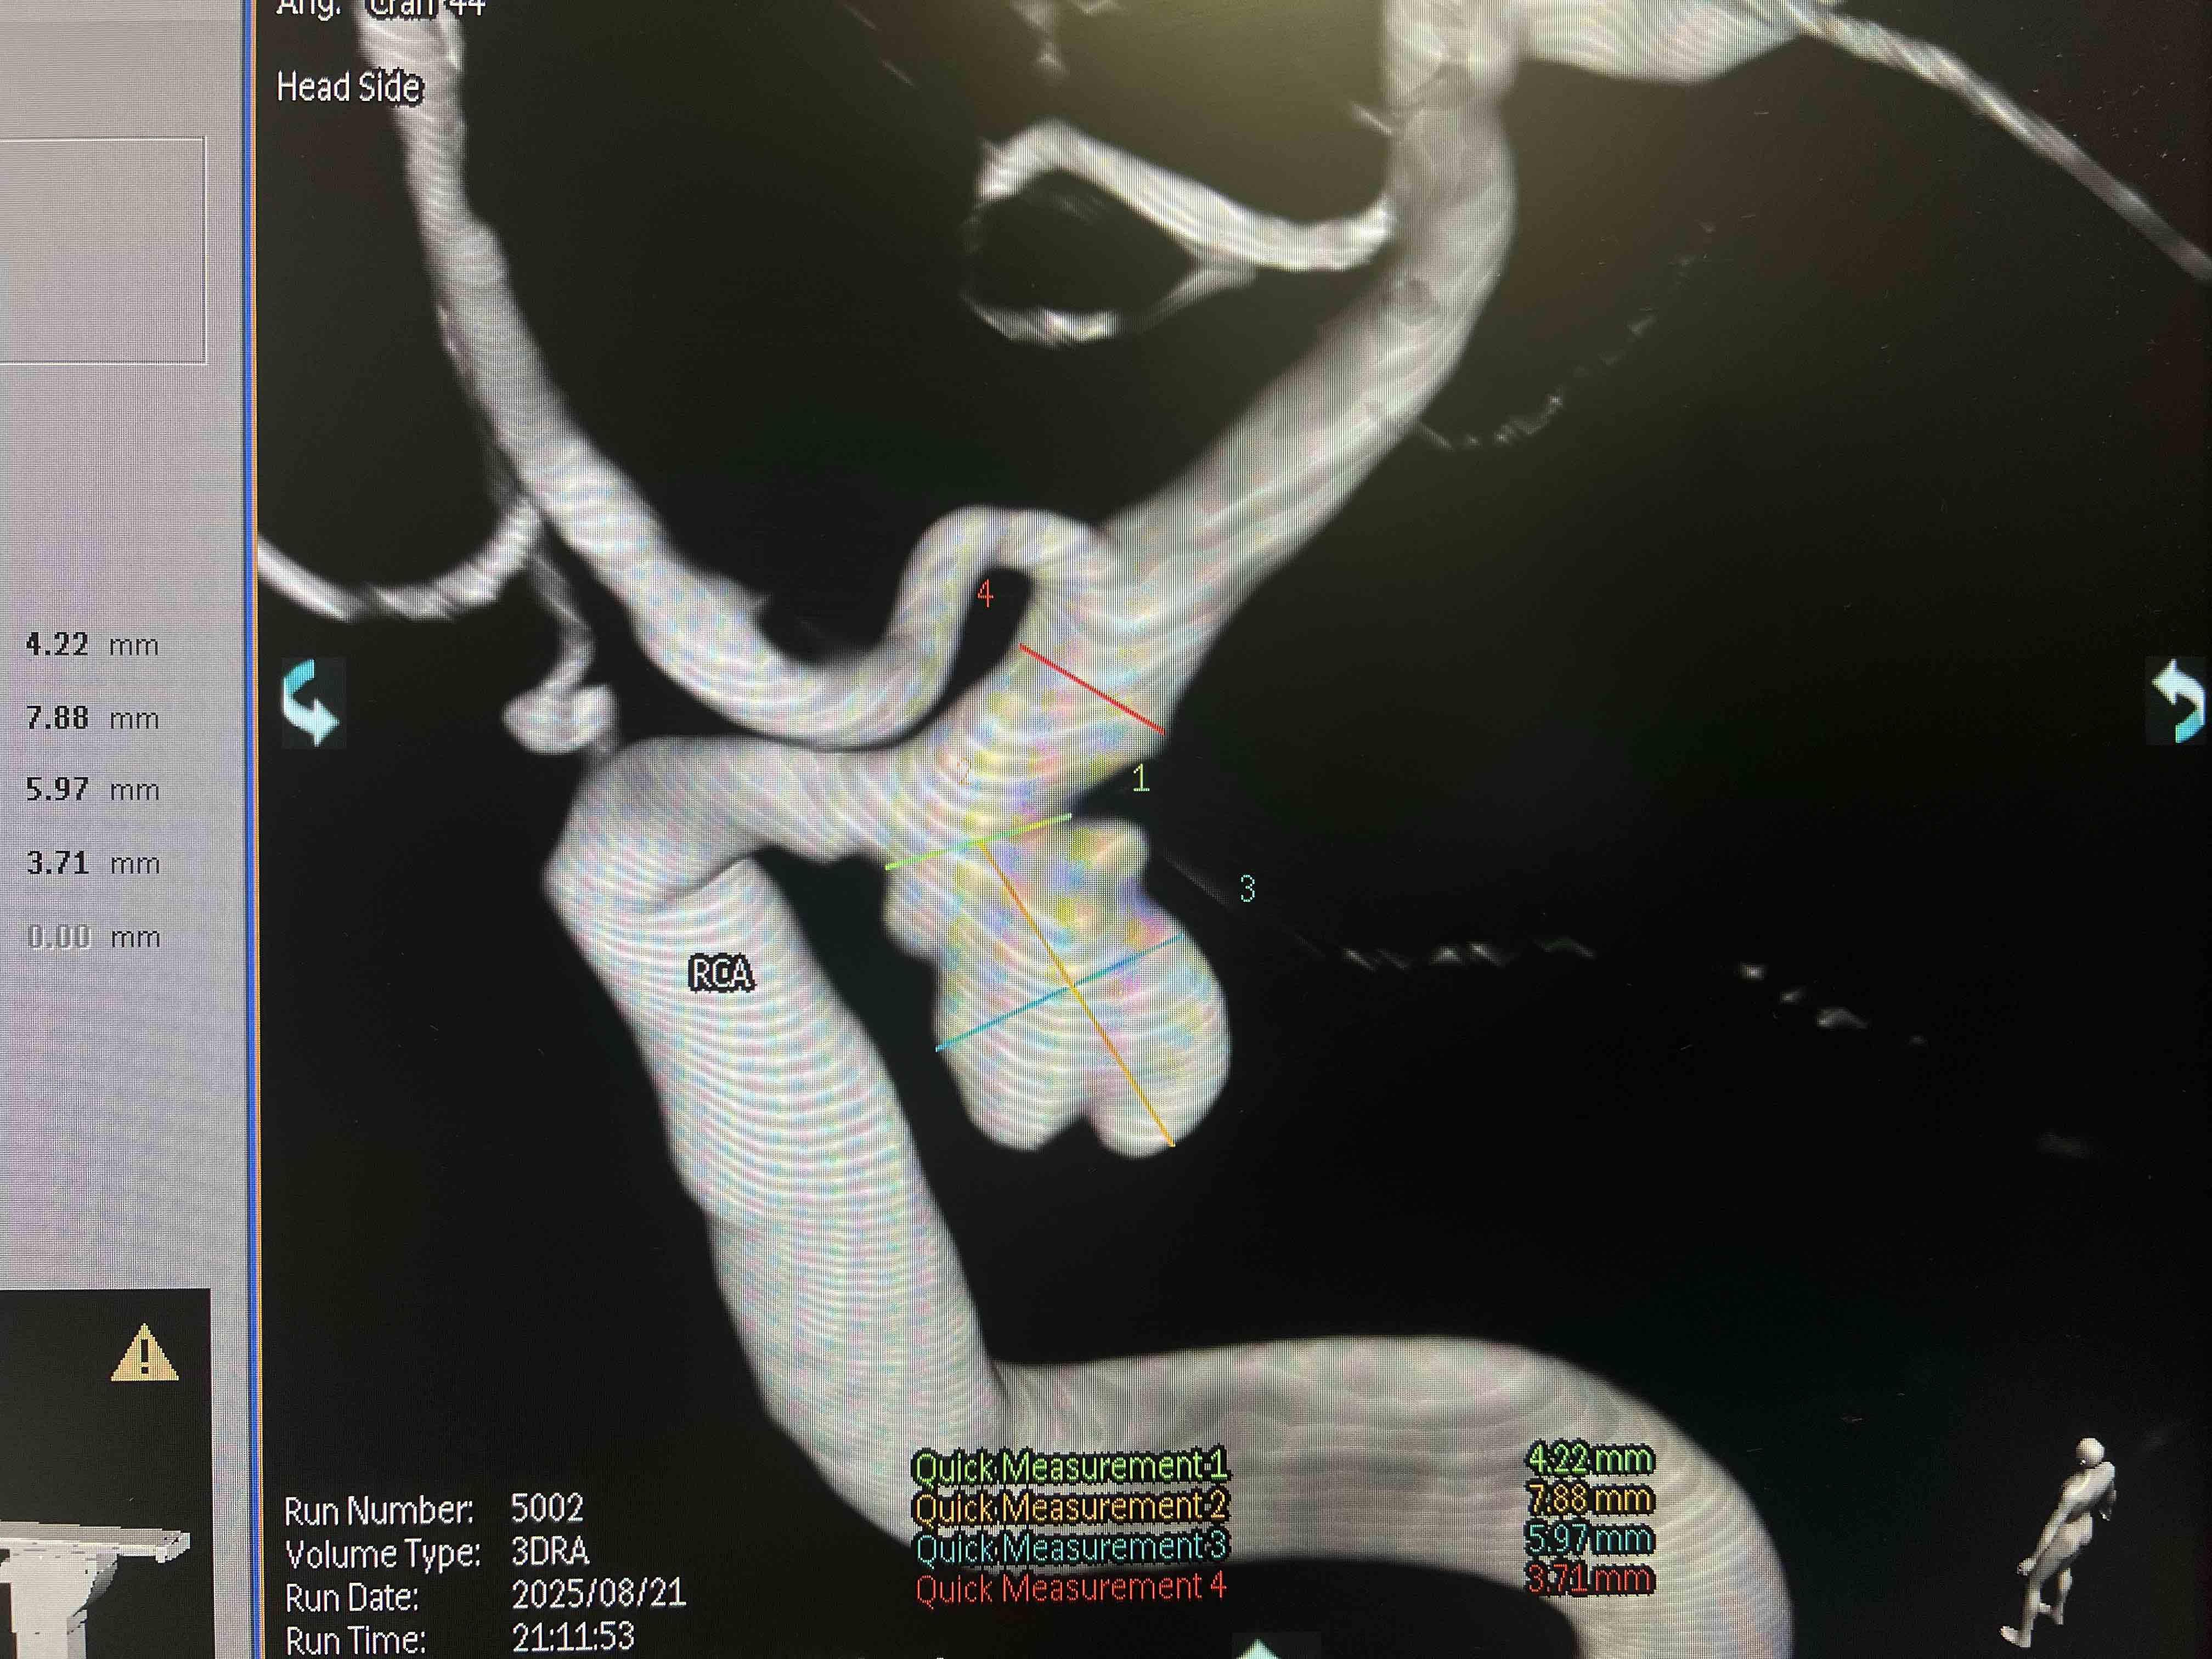

您可能聽說過“腦動(dòng)脈瘤”這個(gè)名字,但千萬別被它誤導(dǎo)了——它并不是我們通常理解的那種會(huì)擴(kuò)散的腫瘤。實(shí)際上,它是顱內(nèi)動(dòng)脈血管壁上鼓起的一個(gè)脆弱“小包”,就像車胎磨損后鼓起的薄弱氣囊,是血管壁結(jié)構(gòu)出了問題。這個(gè)“小包”的危險(xiǎn)性在于它極其脆弱。想象一下,一旦這個(gè)氣囊破裂,高壓的動(dòng)脈血就會(huì)像決堤的洪水一樣瞬間涌入大腦周圍的腔隙(醫(yī)學(xué)上稱為蛛網(wǎng)膜下腔),導(dǎo)致一種非常兇險(xiǎn)的急癥:蛛網(wǎng)膜下腔出血。這種出血的后果極其嚴(yán)重,被稱為“顱內(nèi)炸彈”毫不為過。統(tǒng)計(jì)顯示,破裂后約有三分之一的人會(huì)不幸喪生;而在幸存者中,很大一部分人會(huì)留下嚴(yán)重且持久的神經(jīng)功能障礙,影響生活能力。更令人擔(dān)憂的是,如果未能及時(shí)得到有效治療,這個(gè)破裂過的“小包”極其容易再次破裂,而每一次破裂都會(huì)帶來更糟糕的結(jié)果。研究發(fā)現(xiàn),大約每50個(gè)人中就有1個(gè)人可能攜帶這種潛在的“不定時(shí)炸彈”。在大多數(shù)情況下,動(dòng)脈瘤體積較小且深藏在大腦深處,絕大多數(shù)人在它破裂前沒有任何感覺,常常是在做頭部CT血管成像(CTA)或磁共振血管成像(MRA)檢查時(shí)才被意外發(fā)現(xiàn)。那么,身體會(huì)給我們發(fā)出警告信號(hào)嗎?在動(dòng)脈瘤沒有破裂時(shí),很多人確實(shí)沒有任何特殊感覺。但如果這個(gè)“小包”長(zhǎng)得比較大,壓迫到附近的神經(jīng),就可能出現(xiàn)一些征兆,比如看東西重影(復(fù)視)、一側(cè)眼皮抬不起來(眼皮下垂)或者眼眶后面持續(xù)疼痛。而一旦動(dòng)脈瘤破裂,最典型的信號(hào)就是突發(fā)的、極其劇烈的頭痛,這種痛感常被描述為“一生中最劇烈的頭痛”、“仿佛腦袋要炸開”。同時(shí),還可能伴隨脖子發(fā)硬、惡心嘔吐、怕光、意識(shí)模糊甚至昏迷。值得慶幸的是,現(xiàn)代醫(yī)學(xué)的發(fā)展為我們提供了精確診斷和有效治療的手段。通過CT血管成像(CTA)或更精確的腦血管造影(DSA),醫(yī)生可以清晰地看到動(dòng)脈瘤的位置和形態(tài)。治療的核心目標(biāo)是在它破裂前或破裂后,將這個(gè)危險(xiǎn)的“小包”隔離起來,阻止血流繼續(xù)沖擊它。主要方法包括開顱手術(shù)用特制的夾子夾閉瘤頸,或者通過微創(chuàng)的介入手術(shù),用彈簧圈或密網(wǎng)支架等材料從血管內(nèi)部填塞瘤腔或重塑血管。面對(duì)腦動(dòng)脈瘤這個(gè)潛在的威脅,“預(yù)防勝于治療”尤為重要。我們能做些什么來降低風(fēng)險(xiǎn)呢?首先,要嚴(yán)格管理好血壓,規(guī)律監(jiān)測(cè)并按醫(yī)囑用藥,因?yàn)楦哐獕菏菍?dǎo)致血管壁損傷和動(dòng)脈瘤形成、破裂的重要推手。其次,堅(jiān)決戒煙是保護(hù)血管健康的關(guān)鍵一步。此外,保持健康的生活習(xí)慣,如均衡飲食、適度運(yùn)動(dòng)、避免過度勞累和情緒劇烈波動(dòng),也對(duì)維護(hù)血管健康大有裨益。腦動(dòng)脈瘤雖然像是潛藏在身體里的“不定時(shí)炸彈”,但記住關(guān)鍵兩點(diǎn):“未破早干預(yù),破裂急搶救”。掌握這些常識(shí),堅(jiān)持科學(xué)防病,對(duì)于有高危因素的人群(如有家族史、長(zhǎng)期高血壓、吸煙者),在醫(yī)生建議下進(jìn)行早期篩查,是守護(hù)大腦健康、降低風(fēng)險(xiǎn)最有力的盾牌。

前交通動(dòng)脈瘤的破裂風(fēng)險(xiǎn)是神經(jīng)外科和神經(jīng)介入領(lǐng)域的重要關(guān)注點(diǎn)。以下是對(duì)其破裂風(fēng)險(xiǎn)的詳細(xì)分析及管理建議:---###一、破裂風(fēng)險(xiǎn)的關(guān)鍵因素1.動(dòng)脈瘤大小????-高危閾值:通常直徑≥7mm風(fēng)險(xiǎn)顯著增加,但前交通動(dòng)脈瘤因解剖位置特殊(血流動(dòng)力學(xué)復(fù)雜),即使<7mm也可能破裂。??-微小動(dòng)脈瘤:約10%~15%的破裂動(dòng)脈瘤直徑<5mm,需結(jié)合其他因素評(píng)估。2.形態(tài)學(xué)特征????-不規(guī)則形狀(如分葉狀、子囊形成)或長(zhǎng)寬比(高度/寬度)>1.6提示血流紊亂,破裂風(fēng)險(xiǎn)升高。??-瘤頸寬度:寬頸動(dòng)脈瘤(頸寬≥4mm)可能更不穩(wěn)定。3.血流動(dòng)力學(xué)因素????-前交通動(dòng)脈區(qū)域受雙側(cè)頸內(nèi)動(dòng)脈血流沖擊,壓力波動(dòng)大,易導(dǎo)致瘤壁應(yīng)力增加。4.患者個(gè)體因素????-高血壓:收縮壓>160mmHg使風(fēng)險(xiǎn)倍增,控制血壓可降低風(fēng)險(xiǎn)。??-吸煙:尼古丁加速血管壁退變,吸煙者破裂風(fēng)險(xiǎn)是非吸煙者的3倍。??-既往出血史:曾有蛛網(wǎng)膜下腔出血(SAH)的患者,其他動(dòng)脈瘤破裂風(fēng)險(xiǎn)更高。??-家族史:家族性動(dòng)脈瘤(尤其一級(jí)親屬)破裂風(fēng)險(xiǎn)增加。5.動(dòng)態(tài)變化????-動(dòng)脈瘤在隨訪中體積增大或形態(tài)改變(如新發(fā)子囊)是破裂的強(qiáng)烈預(yù)警信號(hào)。---###二、風(fēng)險(xiǎn)評(píng)估工具1.PHASES評(píng)分????綜合評(píng)估種族、年齡、血壓、動(dòng)脈瘤大小/位置等因素,預(yù)測(cè)5年破裂概率(低危<3%,中危3%~15%,高危>15%)。2.影像學(xué)特征分析????-CTA/MRA:評(píng)估形態(tài)、瘤壁是否規(guī)則、有無血栓。??-高分辨率MRI:檢測(cè)瘤壁強(qiáng)化(提示炎癥或脆弱性)。??-DSA(金標(biāo)準(zhǔn)):動(dòng)態(tài)觀察血流動(dòng)力學(xué),判斷是否需要干預(yù)。---###三、破裂的臨床表現(xiàn)與危害-突發(fā)癥狀:劇烈頭痛(“雷擊樣頭痛”)、嘔吐、頸強(qiáng)直、意識(shí)障礙。-并發(fā)癥:再出血(24小時(shí)內(nèi)風(fēng)險(xiǎn)最高)、腦血管痙攣(4~14天)、腦積水。-死亡率:首次破裂死亡率約35%,再出血死亡率達(dá)60%~80%。---###四、風(fēng)險(xiǎn)分層與處理策略|風(fēng)險(xiǎn)等級(jí)|特征|處理建議||--------------|----------|--------------||高危???|直徑≥7mm、不規(guī)則形態(tài)、有癥狀、既往SAH史|積極干預(yù)(介入栓塞/手術(shù)夾閉)||中危???|5~7mm、合并高血壓/吸煙|個(gè)體化評(píng)估,建議干預(yù)或密切隨訪(6~12個(gè)月影像復(fù)查)||低危???|<5mm、形態(tài)規(guī)則、無癥狀|控制危險(xiǎn)因素,定期影像監(jiān)測(cè)(1~2年/次)|---###五、預(yù)防與隨訪1.生活方式干預(yù)????-嚴(yán)格控壓(目標(biāo)<140/90mmHg)、戒煙、限酒。??-避免劇烈咳嗽、用力排便等致顱內(nèi)壓驟升的行為。2.隨訪方案????-未治療者:第1年每6個(gè)月行CTA/MRA,穩(wěn)定后每年復(fù)查。??-介入治療后:術(shù)后6個(gè)月、1年復(fù)查DSA,評(píng)估是否復(fù)發(fā)。---###六、總結(jié)前交通動(dòng)脈瘤的破裂風(fēng)險(xiǎn)需結(jié)合解剖、血流動(dòng)力學(xué)及患者個(gè)體化因素綜合判斷。早期識(shí)別高危特征并積極干預(yù)可顯著改善預(yù)后?;颊邞?yīng)遵循??漆t(yī)生建議,權(quán)衡治療風(fēng)險(xiǎn)與獲益,切勿因“無癥狀”而忽視隨訪。若有突發(fā)劇烈頭痛或神經(jīng)功能障礙,需立即就醫(yī),爭(zhēng)取在“黃金時(shí)間窗”內(nèi)救治。